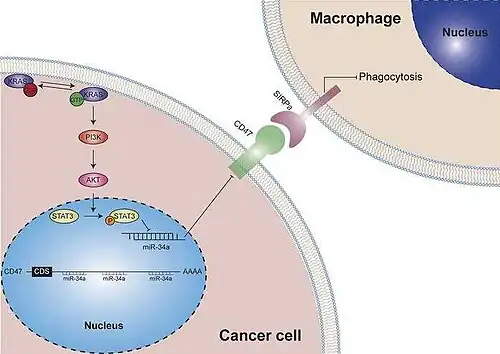

Mutação KRAS

Em 1982, Weinberg e Barbacid isolaram um gene de linhagens celulares de câncer de bexiga humano, identificado como homólogo humano do gene RAS, denominado HRAS e, outro encontrado em células de câncer de pulmão humano, denominado KRAS [41]. Funcionalmente, o RAS é um tipo de proteína reguladora ligada à membrana (proteína G) que se liga ao nucleotídeo guanina, pertencente à família das guanosina trifosfatoses (GTPases), atuando como um interruptor binário de guanosina difosfato (GDP)/trifosfato (GTP), controlando a transdução de sinal de receptores de membrana ativados para moléculas intracelulares [42]. A ligação KRAS-GTP causa mudança de conformação ativando o KRAS que se liga às suas moléculas a jusante para mediar uma série de cascatas de sinalização. Podendo ser ativadas por fatores de crescimento, quimiocinas, Ca2+ ou receptor tirosina quinase (RTK), esta proteína pode ativar múltiplas vias de sinalização. Em contraste, a ligação GDP-KRAS, aumenta a atividade GTPase, mantendo-o em estado inativo [41].

Membro comumente mutado da família RAS, é considerado o condutor genético oncogênico mais comum em cânceres humanos, tendo seu perfil das mutações KRAS diferindo entre os diferentes tipos de câncer. Alterações causadas por mutações impedem a interação do KRAS com GAPs e a hidrólise do GTP ligado ao KRAS, deixando-o em um estado constantemente ativo, podendo afetar, também, a interação com seus efetores [42].

Em tumores, não há apenas a dedicação às suas características intrínsecas, como sobrevivência e proliferação, mas também em relação a seu microambiente tumoral (TME), afetando especialmente as células imunes e resultando na progressão do tumor e no escape imunológico [42]. O TME, na presença de mutações no KRAS, aparece inflamatório e infiltrado por múltiplas células do sistema imunológico devido seus altos níveis de fatores inflamatórios de citocinas e quimiocinas mediados pela sinalização KRAS, demonstrando que a super ativação desta sinalização aumenta a secreção de interleucinas, necessárias para o início e progressão do tumor e importante para o crosstalk entre tumores e inflamação.[41]

As mutações do KRAS também desempenham um papel na evasão imunológica, uma vez que afeta as células do sistema imunológico no TME, na aquisição e no recrutamento de fenótipos inibitórios de células do sistema imunológico. Nos tumores com mutação KRAS, outros oncogenes ou genes supressores de tumor também podem ser anormais e participar no escape imunológico juntamente com a mutação KRAS [41]. Dessa maneira, quando combinado com moléculas a montante, temos: a reativação do KRAS e seus efetores a jusante induzidos pelos receptores adaptativos de tirosina quinases (RTKs), mecanismos de resistência aos medicamentos, portanto a combinação de inibidores do KRAS (G12C) e RTKs direcionados aos medicamentos pode ser uma estratégia terapêutica promissora. Combinado com moléculas a jusante, temos o KRAS reticulado com várias vias de sinalização, atuando na sobrevivência e proliferação celular, em vista da sua influência na função do KRAS em diferentes graus, como a perda de atividade, a qual necessita do KRAS para a tumorigênese, inibindo o crescimento oncogênico.[42]

Assim, uma exploração mais aprofundada da resistência intrínseca deve ser realizada para identificar biomarcadores que indiquem a população apropriada e o tipo de tumor na clínica. Entretanto, o desafio comum aos medicamentos específicos é o aparecimento de resistência adquirida, portanto, maiores investigações são claramente necessárias para elucidar de forma abrangente os mecanismos de resistência adquirida para obter opções de tratamento ideais.[41]